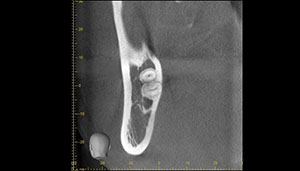

左下親知らずがたまに痛み、

できれば痛くなく抜きたい症例

- 抜歯前写真(CT画像)

| 抜歯内容 | 左下親知らずが横向きになって半分埋まっている状態だったため、麻酔を行い、親知らずの奥の歯ぐきに切開をいれ、歯が囲んでいる骨を削り、歯の頭の部分を削って出し、その後根の部分に器具をかけて抜歯しました。 親知らずが一部神経に近い部分があったため、術後に麻痺が出る可能性がありました。このケースでは事前にCTを撮影し、歯の位置、根の方向、神経との距離を確認していたため、幸い麻痺が出ることはありませんでした。 術後1週間経過して糸取りをして治療は終了となりました。抜歯後3日間は腫れと痛みで大変だったが、糸取りをする頃には痛みも腫れも無くなったと患者さまも喜んでおられました。 |